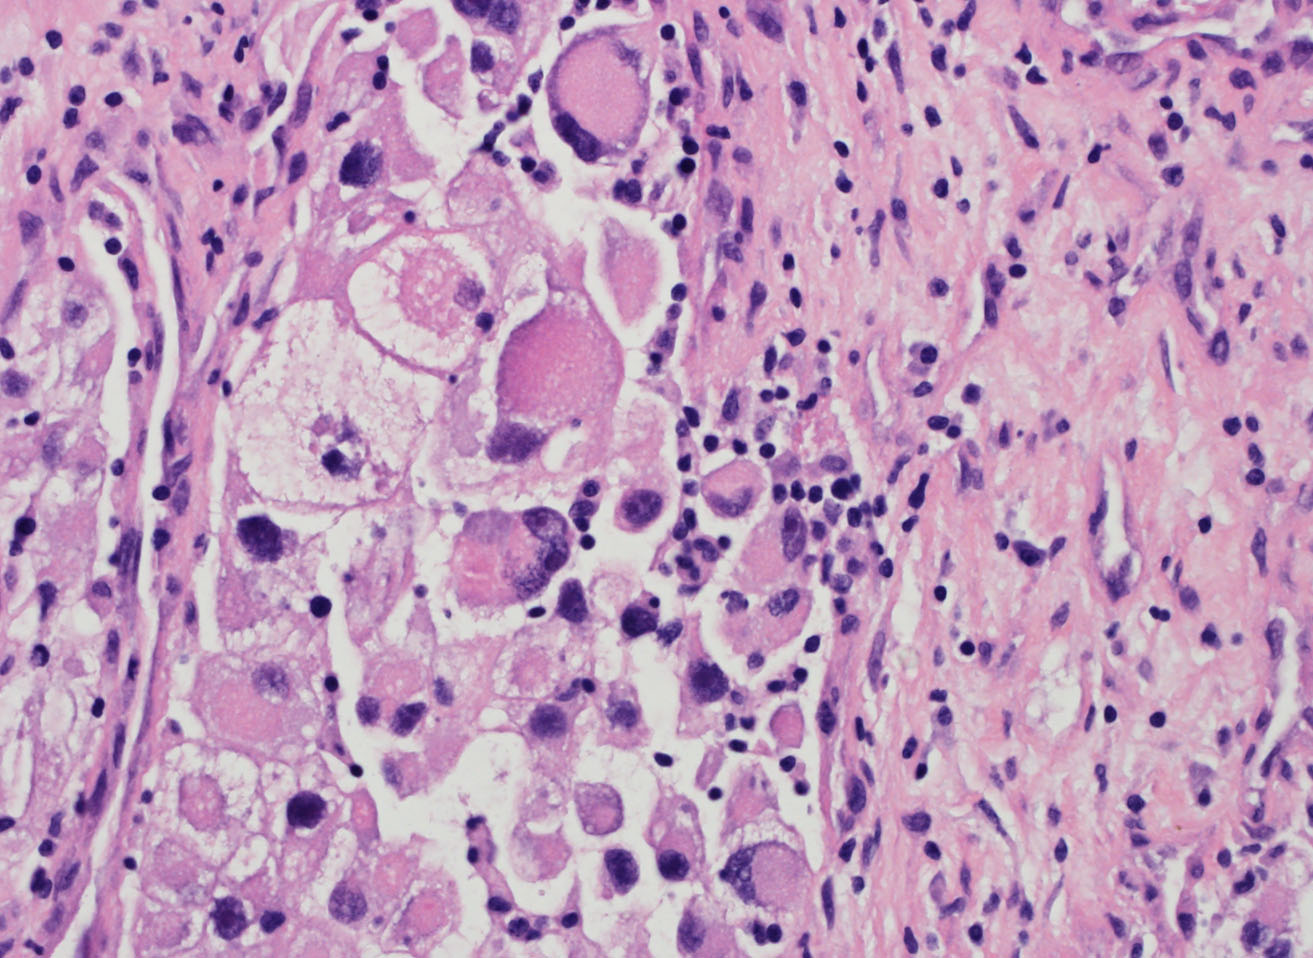

Consensus grade: WHO/ISUP grade 4

Rhabdoid cells |